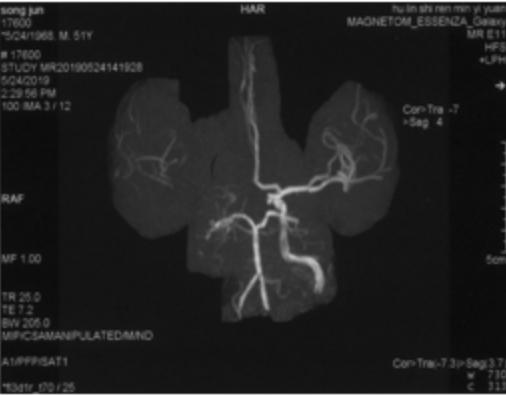

2019-05-24外院头颅MRI+MRA+DWI:右侧基底节区、放射冠、半卵圆中心脑梗死,右侧颈内动脉闭塞(图1)。

图1